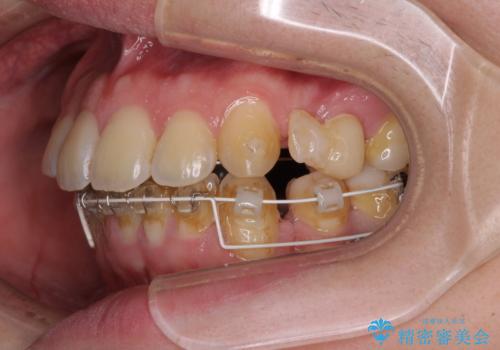

出っ歯と八重歯 目立たない裏側装置でスッキリとした口元に

- ハーフリンガル

目立たない装置を希望されたので、上顎が裏側装置のハーフリンガルを選択し、上下左右の小臼歯(計4歯)を抜歯して矯正治療を行うこととしました。

上下顎で左右差の大きい抜歯矯正を裏側装置で行ったため、非常に時間がかかりましたが、正中位置も良い位置に改善され、気になっていた突出感も解消されました。